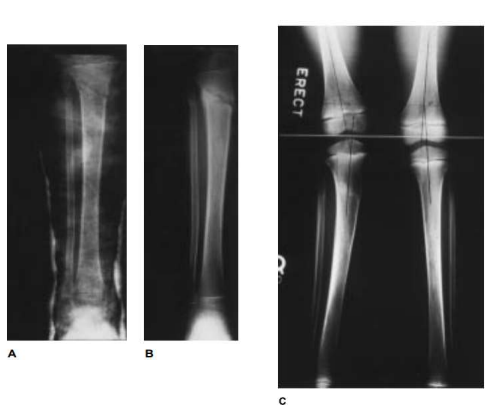

Trauma is probably the most common cause of pathological genu valgum. Damage to the proximal femur or tibia can cause valgus deformity due to reduction or epiphyseal damage and subsequent growth arrest. Salter Harris type III, IV and V fractures in the proximal tibia, as in other parts of the immature bone, are the most dangerous for this. In contrast, some authors have shown that fracture pattern in the distal femur does not predict future developmental problems. . Additionally, the geometry of this epiphysis may affect the ability to achieve adequate anatomical reduction. It is worth noting that hidden epiphyseal injury of the knee may be accompanied by more pronounced fractures in the metaphyseal and diaphyseal region of the tibia and femur, leading to the development of angular deformity. Family members help. Hresko and Kasser6 recommend that all patients with lower extremity injuries receive a comprehensive evaluation as well as a knee electrocardiogram. Another cause of knee valgus is tibial valgus that occurs after proximal tibial metaphyseal fracture (Figure 3). Many reports on this problem have been published since Cozen7 first described it in 1953. The exact cause of the abnormality is still unknown, but several theories have been proposed. Cozen believes that this problem is caused by asymmetric stimulation of the proximal tibial epiphyseal plate. Salter and Best10 consider malunion to be the most important factor in the pathogenesis of valgus angulation. Houghton and Rooker11 attempted to cause tibial valgus in rabbits by dividing the anserine and medial periosteum and assumed the binding effect of the negative lateral periosteum as the mechanism. Weber12 surgeon investigated two cases of posterior valgus and found that the foot of the anserine was impinged on the fractured bone and thought that the medial tissue was the cause of the deformity. Recently, Jordan et al.13 reported 7 patients with this deformity, reviewed the main theories regarding the etiology of this problem, and concluded that the most important mechanism was itching in the middle of the tibia due to bone hyperemia. This is a common assumption and is supported by the results of two cases. Green14 reported a case of post-traumatic tibial valgus in which the presence of an asymmetric growth arrest line supported a mechanism for medial proximal tibial overgrowth. Zionts et al.15 reported a case of tibial valgus in which bone scan showed strong radionuclide in the medial

half of the proximal tibial growth plate.

Fig. 3 Serial radiographs showing genu valgum due to inadequate initial reduction of a proximal metaphyseal tibial fracture in a 7-year-old child. A, Inadequate reduction. B, Malunion at the time of cast removal. C, Resultant valgus at 1-year follow-up.